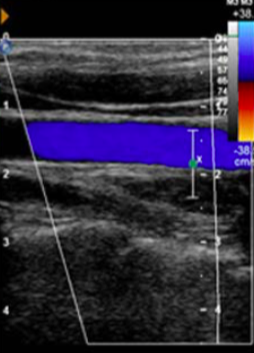

For the following arterial duplex US (DUS) image:

comment on the PRF setting

PRF is set very low

you can tell this based on the velocity range of the color bar (range of 12 cm/s, relatively low setting

recall that PRF value is directly-related to color doppler frequency parameters (and the associated blood velocity)